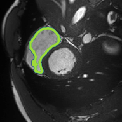

Despite their outstanding accuracy, semi-supervised segmentation methods based on deep neural networks can still yield predictions that are considered anatomically impossible by clinicians, for instance, containing holes or disconnected regions. To solve this problem, we present a Context-aware Virtual Adversarial Training (CaVAT) method for generating anatomically plausible segmentation. Unlike approaches focusing solely on accuracy, our method also considers complex topological constraints like connectivity which cannot be easily modeled in a differentiable loss function. We use adversarial training to generate examples violating the constraints, so the network can learn to avoid making such incorrect predictions on new examples, and employ the Reinforce algorithm to handle non-differentiable segmentation constraints. The proposed method offers a generic and efficient way to add any constraint on top of any segmentation network. Experiments on two clinically-relevant datasets show our method to produce segmentations that are both accurate and anatomically-plausible in terms of region connectivity.